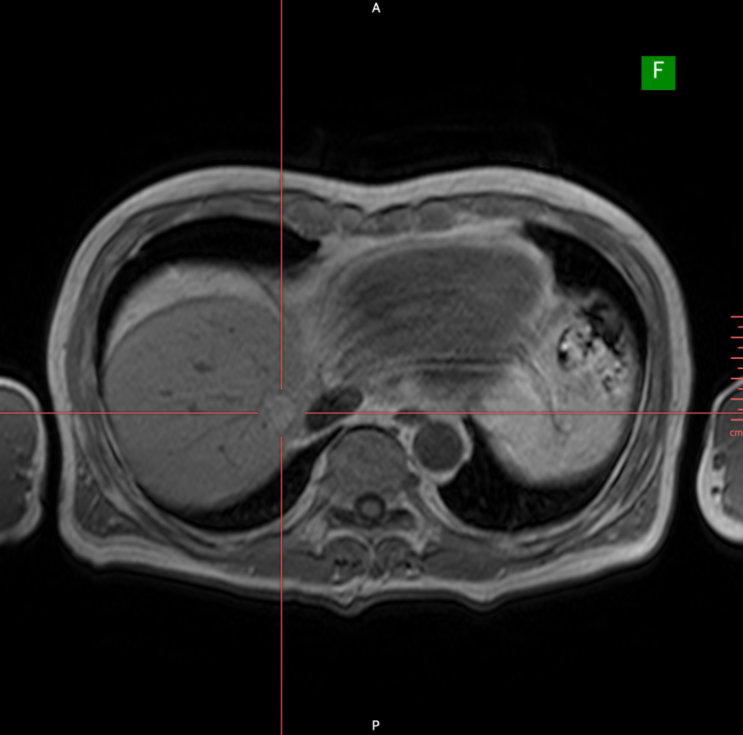

환자분은 보다 정밀한 지단을 위해 먼저 정맥 주입형 조영제를 사용한 프리모비스트(Primovist, 고프리텔 MRI)를 사용한 2가지 MRI 검사를 시행하였습니다. 복부 MRI에서 왼쪽 간엽에 약 1.7cm크기의 고에코 결절이 발견되었고, 추가적인 정밀 확인을 위해 복부CT 검사를 시행하였습니다. 복부 MRI에서 왼쪽간엽에 간암 양상의 병변으로 생각되는 조영 양상을 보였습니다.

• 복부 MRI T1 영상 - 간 좌엽 종양 확인 복부 MRI T1 영상 - 간 좌엽 종양 확인

• 복부 MRI T2 영상 - 조영 후 간 종양 경계 뚜렷함 복부 MRI T2 영상 - 조영 후 간 종양 경계 뚜렷함

• 프리모비스트 MRI - 간암의 전형적인 조영 양상 프리모비스트 MRI - 간암의 전형적인 조영 양상